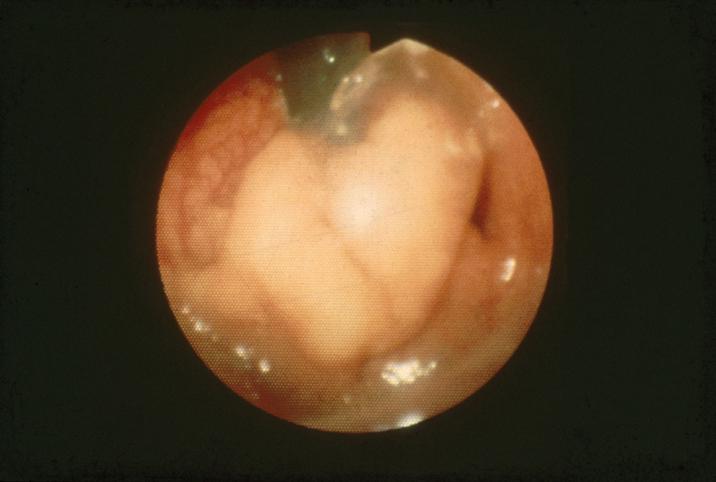

조기암을 동반한 대장 융모종양

[Image-ID:2596]

부위(장기별)

대장/S상

검사방법

내시경

종양의 육안분류

0형(표재형)/I형(Is)

종양의 최대경(밀리미터)

35~40

종양의 심달도

sm